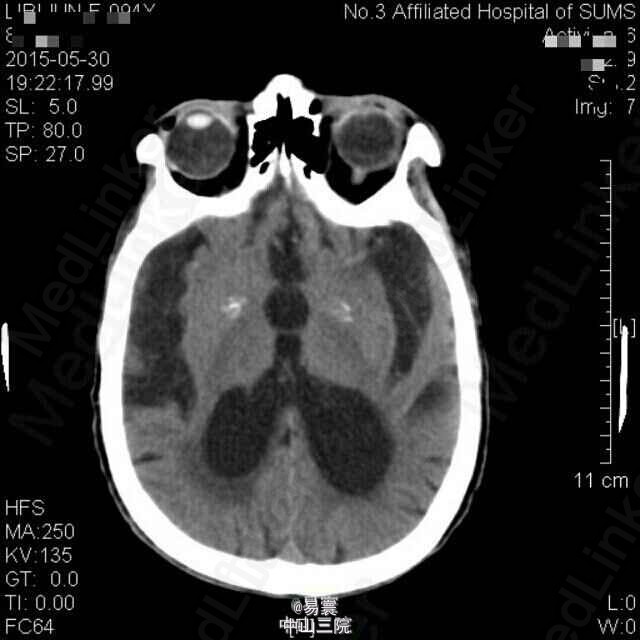

入院查体:神清,消瘦貌,双肺呼吸音稍粗,可闻及少量湿罗音,心律齐。昏睡至浅昏迷貌,呼叫无睁眼,压眶疼痛刺激可定位,肢体疼痛刺激有回缩,双侧瞳孔等大,直径2mm,未见对光反射,眼球居中,未见眼震,双侧额纹、鼻唇沟对称,平卧位双侧上肢可维持45度平伸3-4秒,双下肢可保持屈膝位,不能抬离床面,双侧腱反射减退,双下肢病理征阳性。脑膜刺激征阴性,余查体不能配合。 辅助检查: 1、入院辅助检查:头颅CT平扫(2015-05-30,我院):1、双侧额顶叶、半卵圆中心、侧脑室旁、放射冠及基底节区多发缺血变性或梗塞灶,建议MRI+DWI进一步检查。2、老年脑。3、双侧颈内动脉硬化。胸部螺旋CT平扫(2015-05-30,我院):1.双肺炎症,双肺下叶轻度支气管扩张,建议治疗后复查。2.左肺下叶外基底段钙化灶。3.双侧少量胸腔积液。4.心包少量积液,主动脉硬化。5.肝右叶小囊肿可能。6.甲状腺双侧叶所见,建议进一步检查。 2、入院5天后突发意识障碍查头颅CT示:1、双侧侧脑室、第三脑室积血,并广泛蛛网膜下腔出血。2、双侧额顶叶、半卵圆中心、侧脑室旁、放射冠及基底节区多发缺血梗塞灶,建议MRI+DWI进一步检查。3、老年脑。4、双侧颈内动脉硬化。